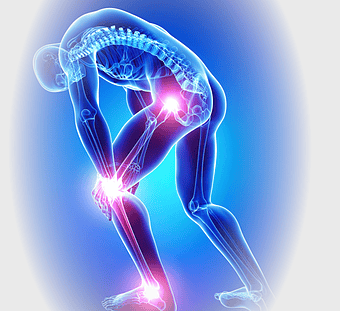

knee pain illustration, osteoarthritis joint pain, medical pain management, violet medical, skeletal joint health, chronic pain therapy, human anatomy injury -